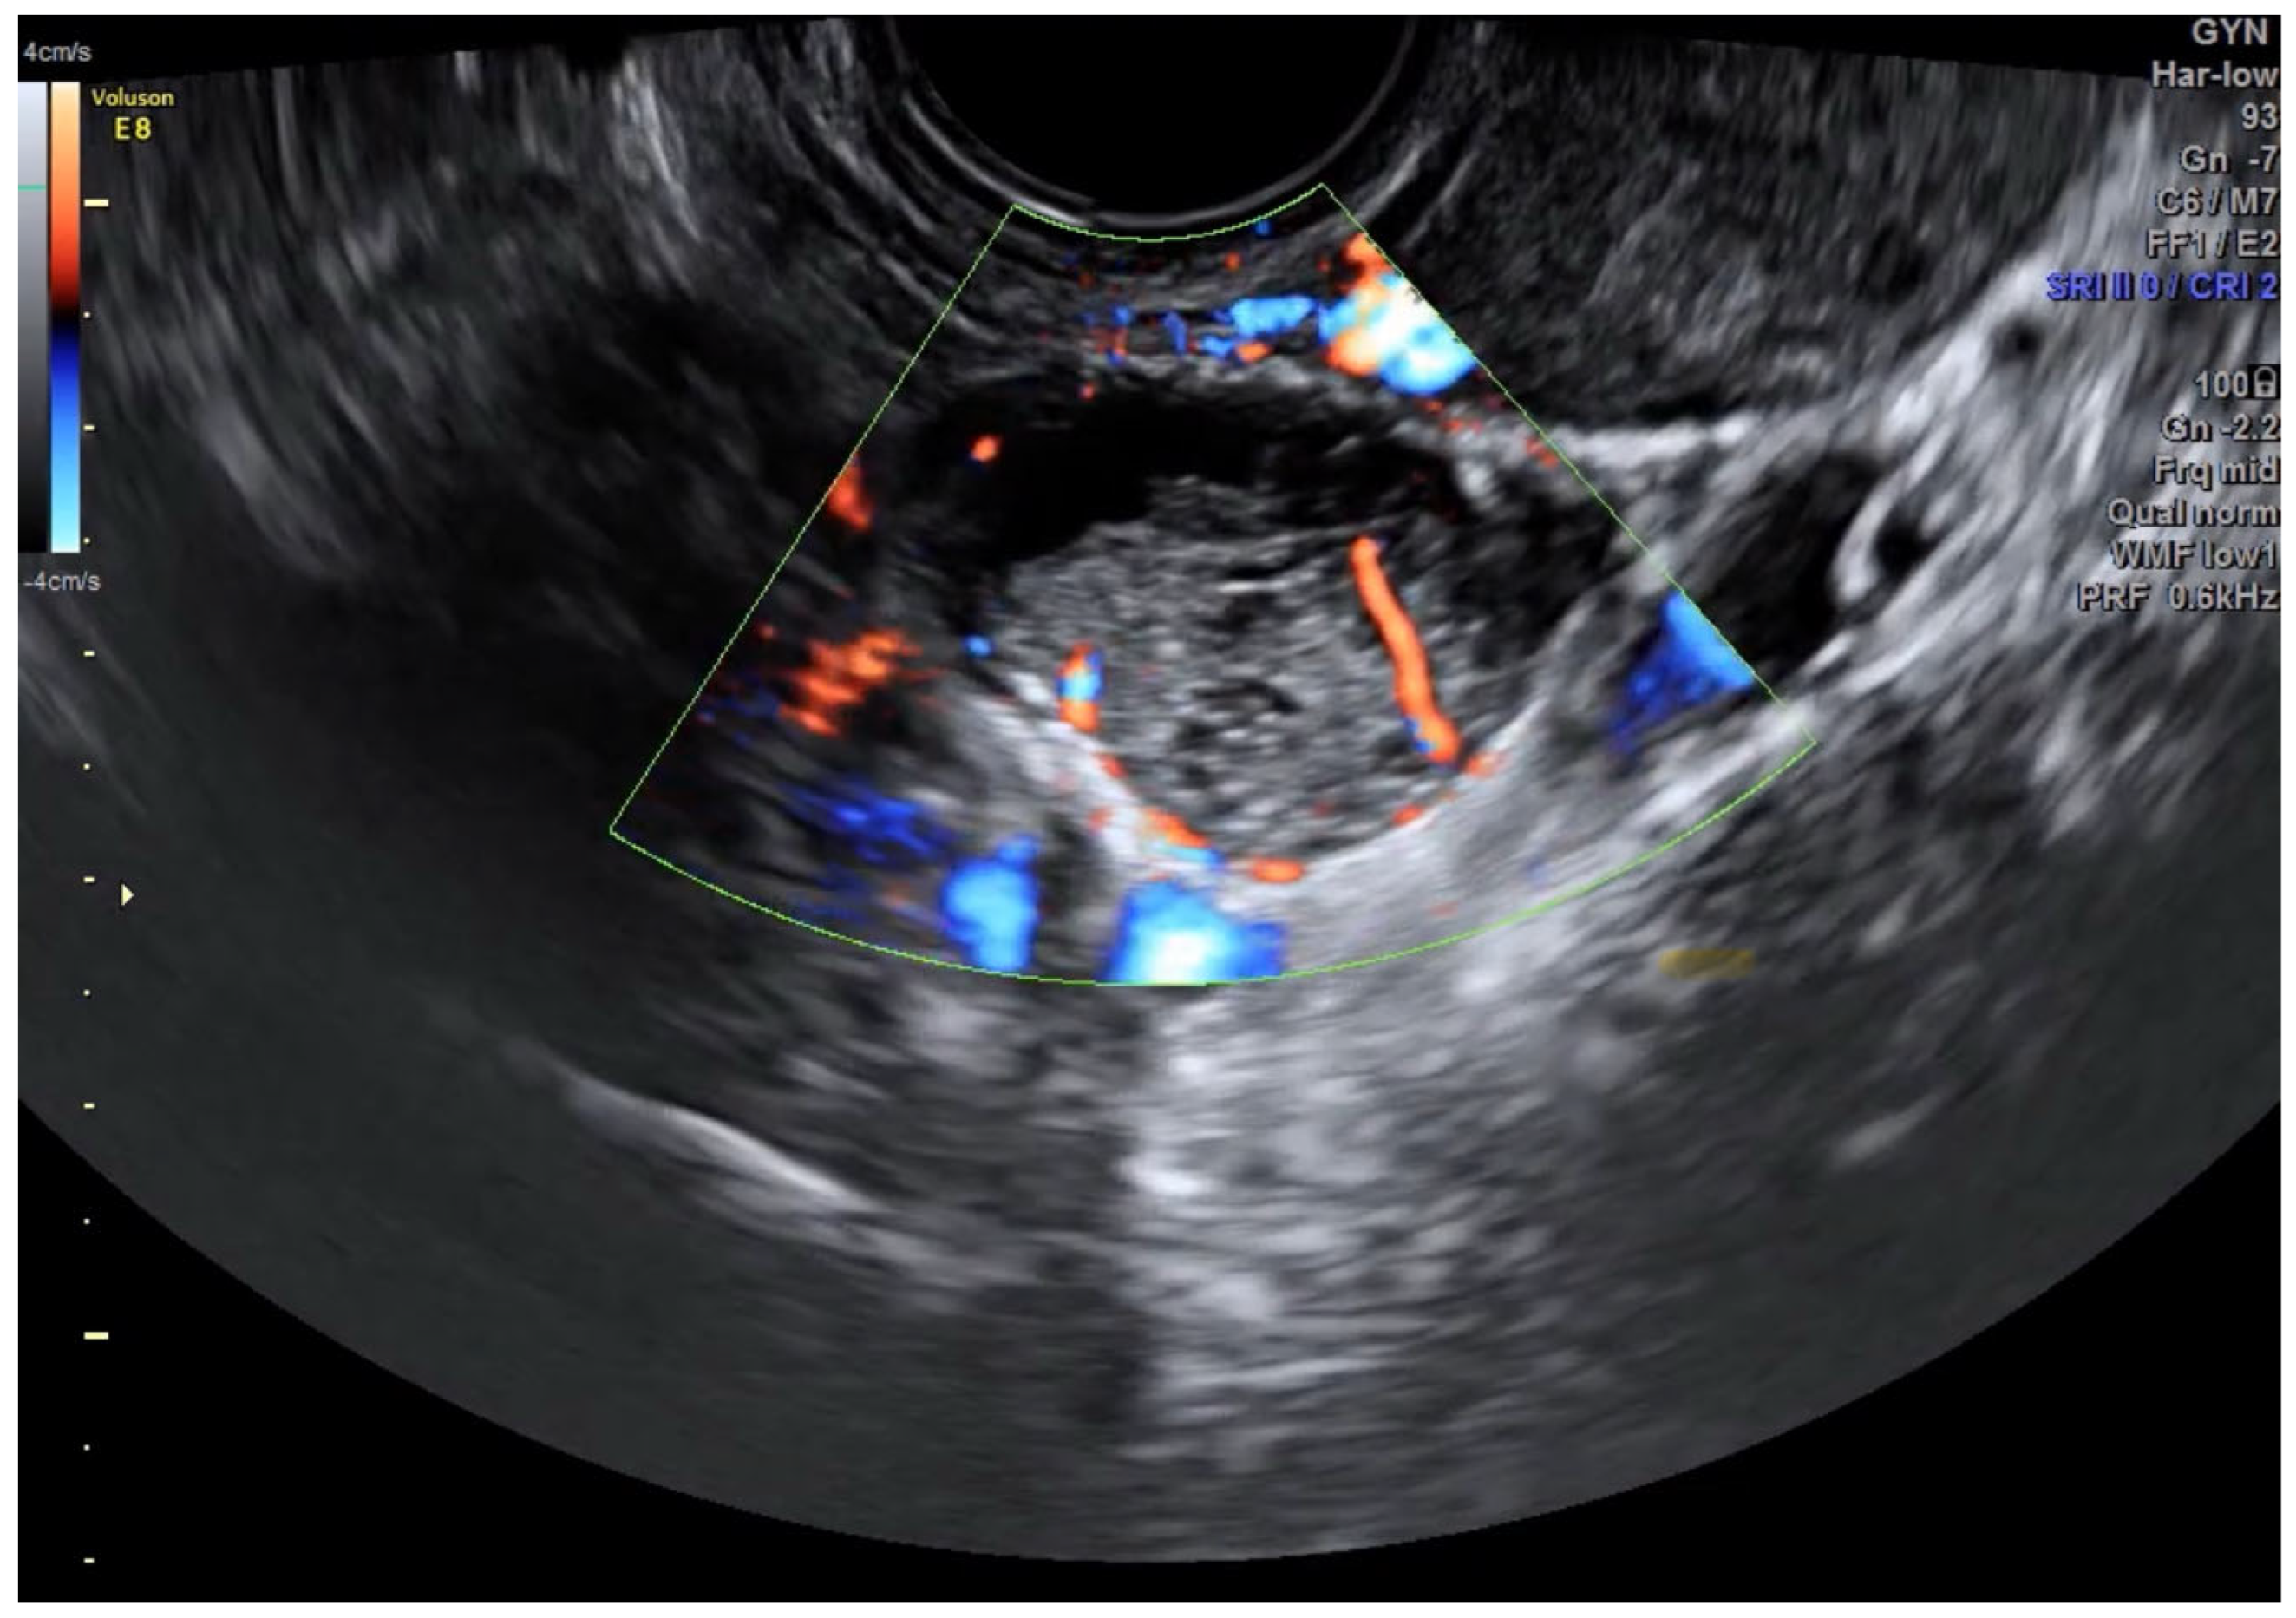

- Borderline ovarian tumors; a paradigm shift

- Pelvic saline infusion (500 mL) creates an acoustic window for enhanced ultrasound transmission.

- Transvaginal or laparoscopic probes provide multiplanar tumor localization.

- Laparoscopic instruments mark lesion boundaries under dual visual-sonographic guidance.

- Diathermy delineates precise resection margins before ultrasound-monitored excision.